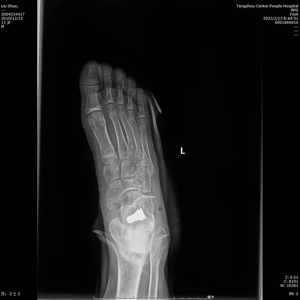

術(shù)中C型臂透視見:制動器位置良好,模擬左足負重試驗,患者足弓恢復(fù)良好。整個手術(shù)時間短,創(chuàng)傷小,見效快,僅用時30分鐘,微創(chuàng)刀口1cm,出血量不足5ml。術(shù)后左足石膏固定,2天后出院。?

(術(shù)后X線)